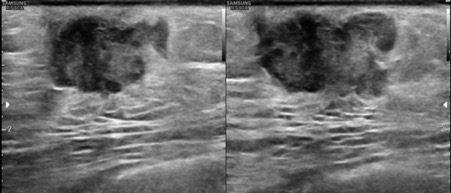

Bilateral Digital mammography , Craniocaudal (CC) and Mediolateral oblique (MLO) view revealed an irregular , high density mass with indistinct margin in retroareolar region with retracted nipple. No microcalcifications was seen. No significant axillary lymph nodes were present. Ultrasound of left breast showed an irregular, heterogeneously hypoechoic mass with indistinct margin and mild posterior acoustic enhancement, measuring about 2.5x1.9x1.3cm in retroareolar region. Internal vascularity was increased on colour doppler. On strain sonoelastogram, the mass showed increased stiffness suggestive of hard consistency. The imaging features are highly suspicious for male breast cancer and thus the mass was classified as BIRADS category 5 lesion and Ultrasound guided biopsy was advised. Patient underwent left modified radical mastectomy and final histopathological report was Invasive Lobular carcinoma. No nipple or lymphovascular invasion was identified.

The imaging features are highly suggestive of male breast cancer and thus the mass was classified as BIRADS category 5